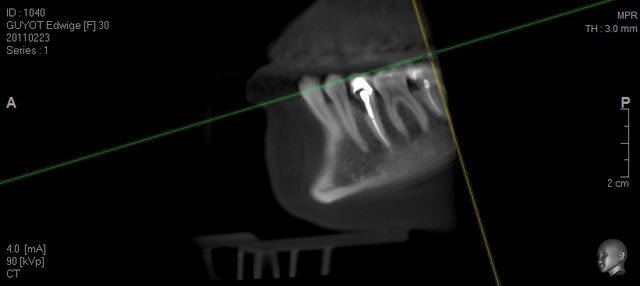

voilà des images de tout les jours....

Guyot pr 2 pqmexp - Eugenol

Guyot pr 3 rztfoz - Eugenol